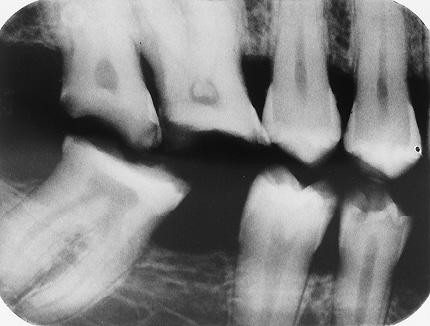

4. In the X ray bellow for which jaw periodontal bone loss is evident?